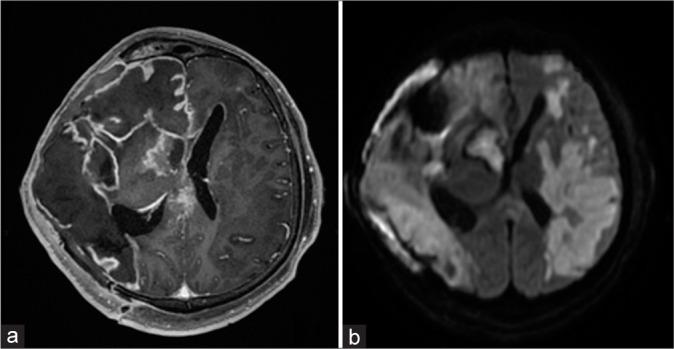

CASE DESCRIPTION

Clinical case of a 58-year-old man who developed an abscess in the chiasmosellar region and an associated mycotic aneurysm of the right middle cerebral artery (MCA) and intracerebral hemorrhage. Microsurgical clipping of the fusiform-ectatic aneurysm of the right MCA in the conditions of rupture was performed. An extra-intracranial micro anastomosis was formed on the right. An open biopsy of the neoplasm in the chiasmosellar region was made. The neoplasm was yellow and destroyed the bone plate of the skull base. Biopsy results: Mycotic lesion (aspergillosis). The analysis of surgical treatment for mycotic aneurysms in the acute period of hemorrhage in patients with aspergillosis revealed a high rate of lethality. The issue of the feasibility and effectiveness of complicated revascularization interventions in the patients with hemorrhage and aspergillosis remains unsolved.

一名58岁男性的临床病例,其在视交叉区域出现脓肿,并伴有右侧大脑中动脉(MCA)霉菌性动脉瘤和脑出血。在动脉瘤破裂的情况下,对右侧MCA的梭形扩张性动脉瘤进行了显微手术夹闭。在右侧进行了颅外-颅内微血管吻合。对视交叉区域的肿瘤进行了开放性活检。肿瘤呈黄色,破坏了颅底骨板。活检结果:霉菌性病变(曲霉病)。对曲霉病患者出血急性期霉菌性动脉瘤的手术治疗分析显示死亡率很高。出血合并曲霉病患者复杂血管重建干预措施的可行性和有效性问题仍未解决。